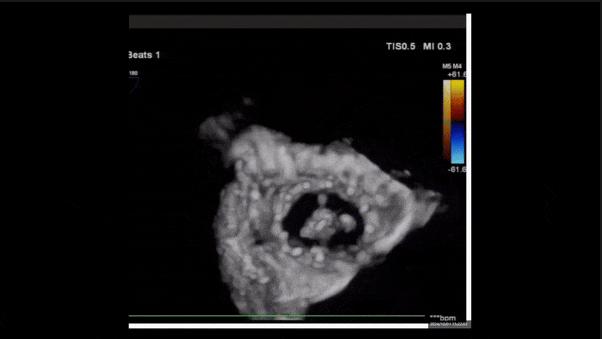

術后三維超聲

術后即刻經食道超聲可見,三尖瓣假體瓣膜位置合適,牛心包瓣葉運動狀態良好,開閉正常,瓣周及瓣葉對合緣處未見明顯返流,心電圖及心包狀態較術前無明顯變化。